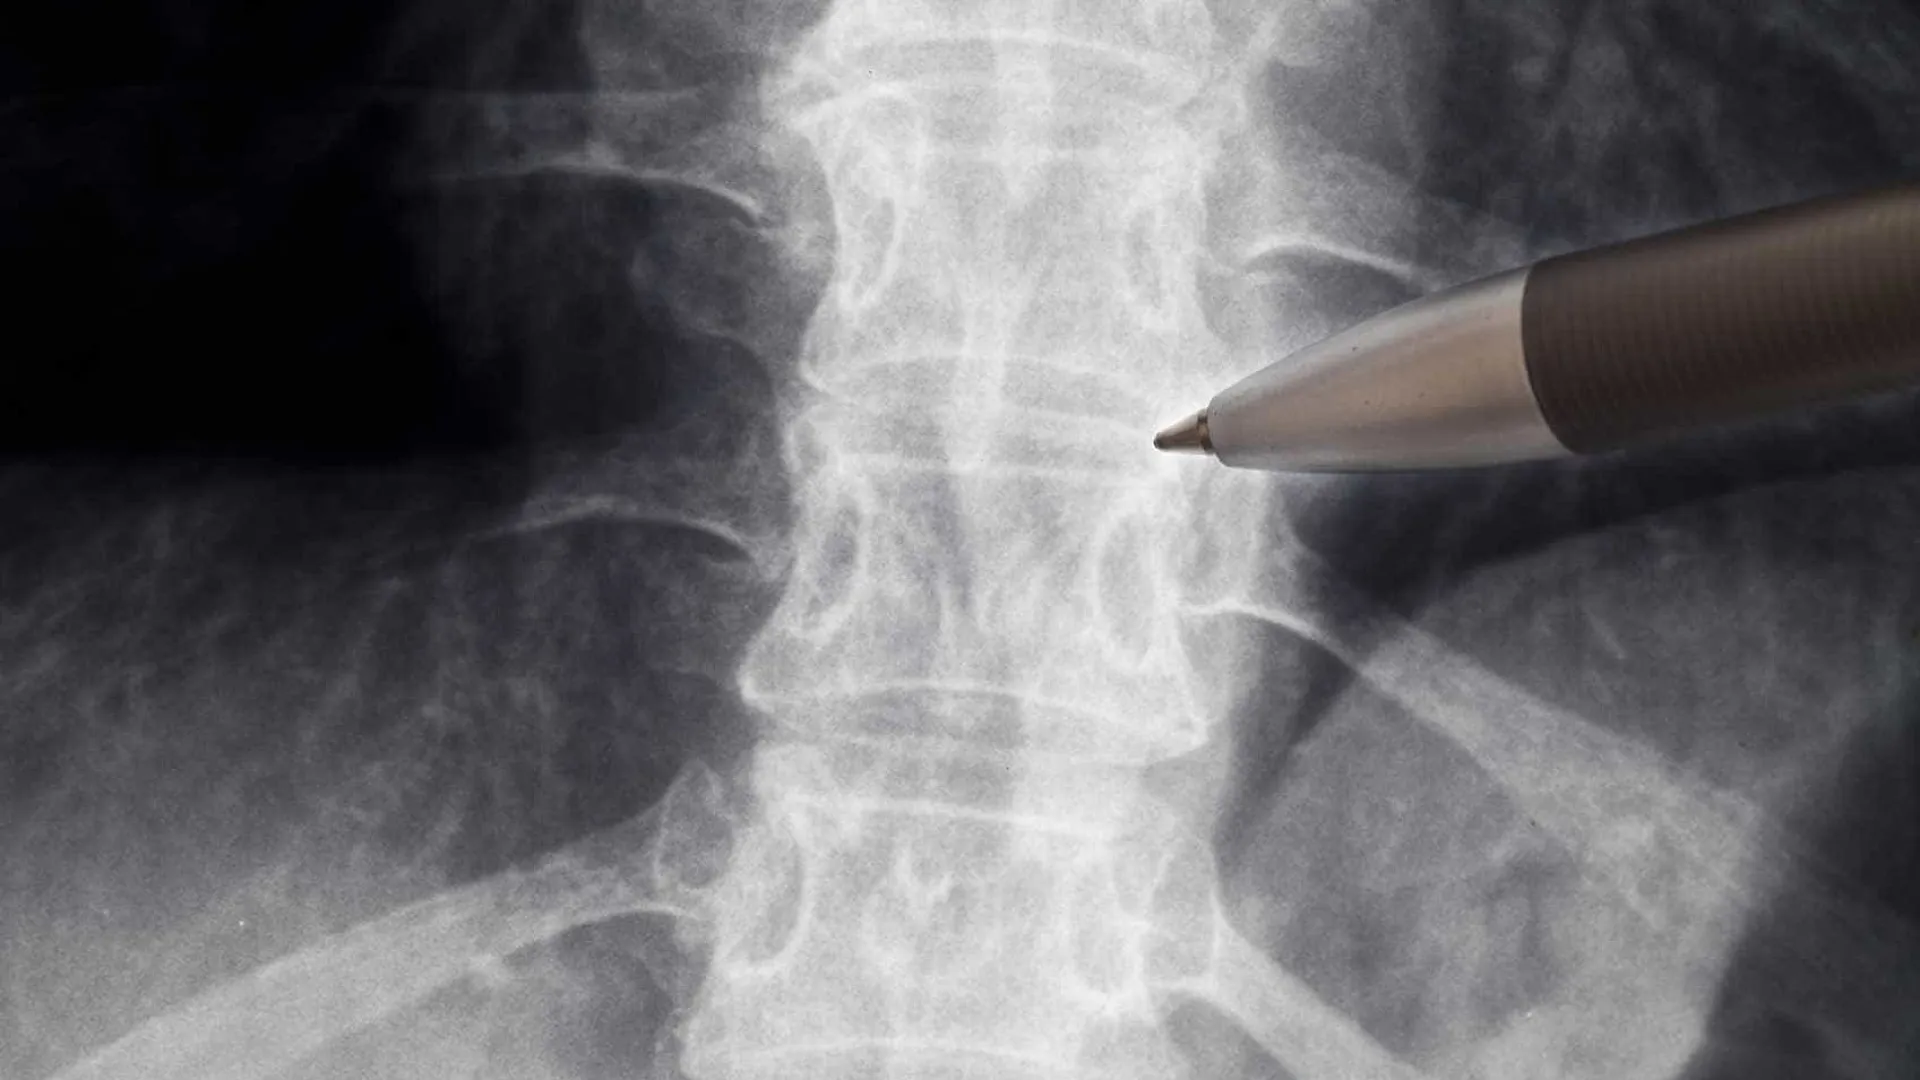

Neurologistas alertam para falta de evidências sobre ação da polilaminina em lesão medular